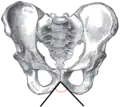

![]() Male pelvis (pubic arch labeled at bottom center) | |

Male subpubic angle